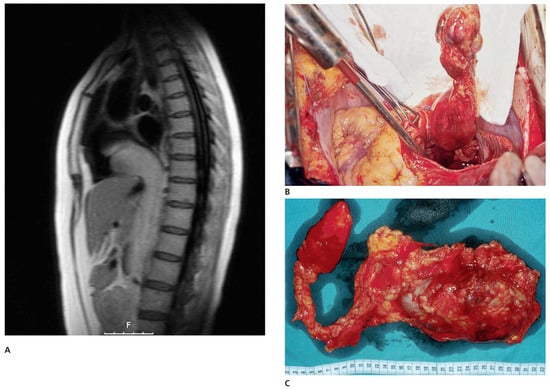

A patient with Morbus Behçet was admitted with severe symptomatic aortic regurgitation caused by aortitis that mimicked infective endocarditis. After aortic valve replacement and antibiotic treatment, regurgitation and systemic inflammation recurred....